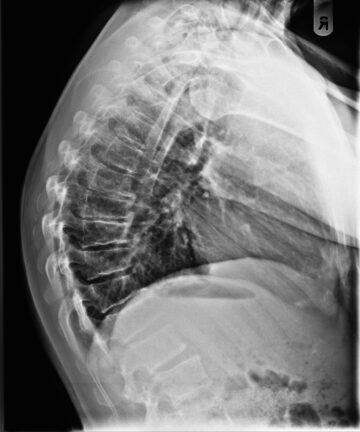

تقوس الجزء العلوي من منتصف الظهر : كيف يؤثر على الرقبة والعمود الفقري عند المراهقين؟ يعاني بعض المراهقين من اعوجاج العمود الفقري المراهقي مجهول السبب (AIS)، وهو أحد أكثر اضطرابات العمود الفقري شيوعًا أثناء

تقوس منتصف الظهر واعوجاج العمود الفقري: كيف يؤثر على شكل الجسم وحركة الفقرات؟ يُعد اعوجاج العمود الفقري عند المراهقين (الجنف) من أكثر مشكلات النمو شيوعًا خلال فترة المراهقة. وغالبًا ما يلاحظ الأهل أن أحد